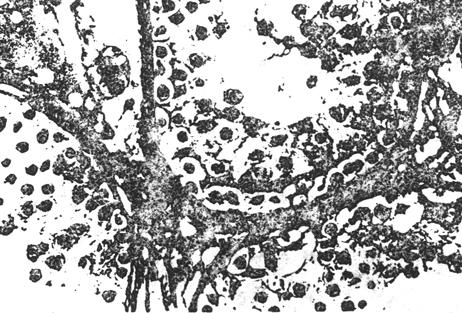

②生精功能低下:曲细精管尚有各级生精细胞,但其数量和层次均有不同程度的减少,细胞排列紊乱。依病变的程度可分为轻、中、重度。轻度约有45%曲细精管病变,但精原细胞基本正常;中度约45~75%以上曲细精管病变,精原细胞缺如基底膜纤维增生少数有透明样变;重度病变很难恢复生育能力。

图8-3-4 生精功能低下,曲细精管生精细胞层次数量减少,排列紊乱